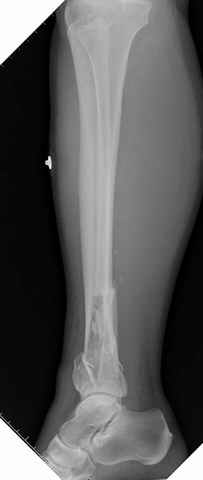

На снимках варианты фиксации малоберцовой:

№ 6-11 при pilon percutaneus fixation